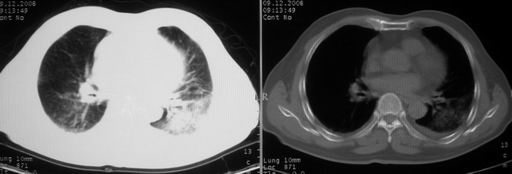

男,78岁,咳嗽、咳痰、发热入院,抗炎治疗一周后已退热,咳血似痰。

10月3日片: